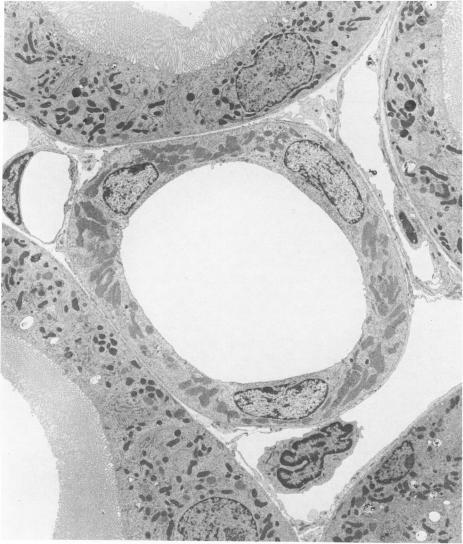

Hypothyroidism in the rat is associated with a decrease in kidney size and weight. We have shown previously that this decrease involves all nephron segments in the cortex and outer medulla and is especially pronounced in the medullary thick ascending limb (mTAL). Therefore, the present study was undertaken for examination of the effect of hypothyroidism on the ultrastructure of the rat mTAL. Hypothyroidism was induced by feeding aminotriazole (ATZ), 0.5 g/kg of food, for 4 weeks. A second group of animals received ATZ plus a daily injection of L-thyroxine (T4). A third group was fed a normal diet only and served as control animals. The kidneys were preserved by in vivo perfusion with 3% glutaraldehyde, and tissue from the inner and outer stripe of the outer medulla was processed for electron microscopy. Morphometric analysis revealed a significant decrease in the cross-sectional area of the mTAL in both the inner and outer stripe of the outer medulla in hypothyroid animals. No changes were observed in the surface density of either the apical or basolateral plasma membranes following ATZ treatment. However, when calculated per millimeter tubule, there was a significant decrease in the surface area (SL) of both the apical and basolateral plasma membranes of the mTAL of hypothyroid animals in comparison with control animals. Simultaneous treatment with T4 prevented the ATZ-induced reduction in both tubule cross-sectional area and in the SL of the plasma membrane. These findings suggest that the observed changes in SL of the plasma membrane of the mTAL are due to a regulatory role of thyroid hormone in membrane proliferation as well as in cell growth in general.

大鼠甲状腺功能减退与肾脏大小和重量的减少有关。我们之前已经表明,这种减少涉及皮质和外髓质的所有肾单位节段,并且在髓质厚升支(mTAL)中尤为明显。因此,本研究旨在检查甲状腺功能减退对大鼠mTAL超微结构的影响。通过喂食0.5 g/kg食物的氨基三唑(ATZ)4周来诱导甲状腺功能减退。第二组动物接受ATZ加每日注射L-甲状腺素(T4)。第三组仅喂食正常饮食并作为对照动物。通过用3%戊二醛进行体内灌注来保存肾脏,并对外髓质内带和外带的组织进行电子显微镜处理。形态计量学分析显示,甲状腺功能减退动物外髓质内带和外带的mTAL横截面积均显著减小。ATZ处理后,顶端或基底外侧质膜的表面密度未观察到变化。然而,当按每毫米小管计算时,与对照动物相比,甲状腺功能减退动物mTAL的顶端和基底外侧质膜的表面积(SL)均显著减小。同时用T4治疗可防止ATZ诱导的小管横截面积和质膜SL的减少。这些发现表明,观察到的mTAL质膜SL的变化是由于甲状腺激素在膜增殖以及一般细胞生长中的调节作用。